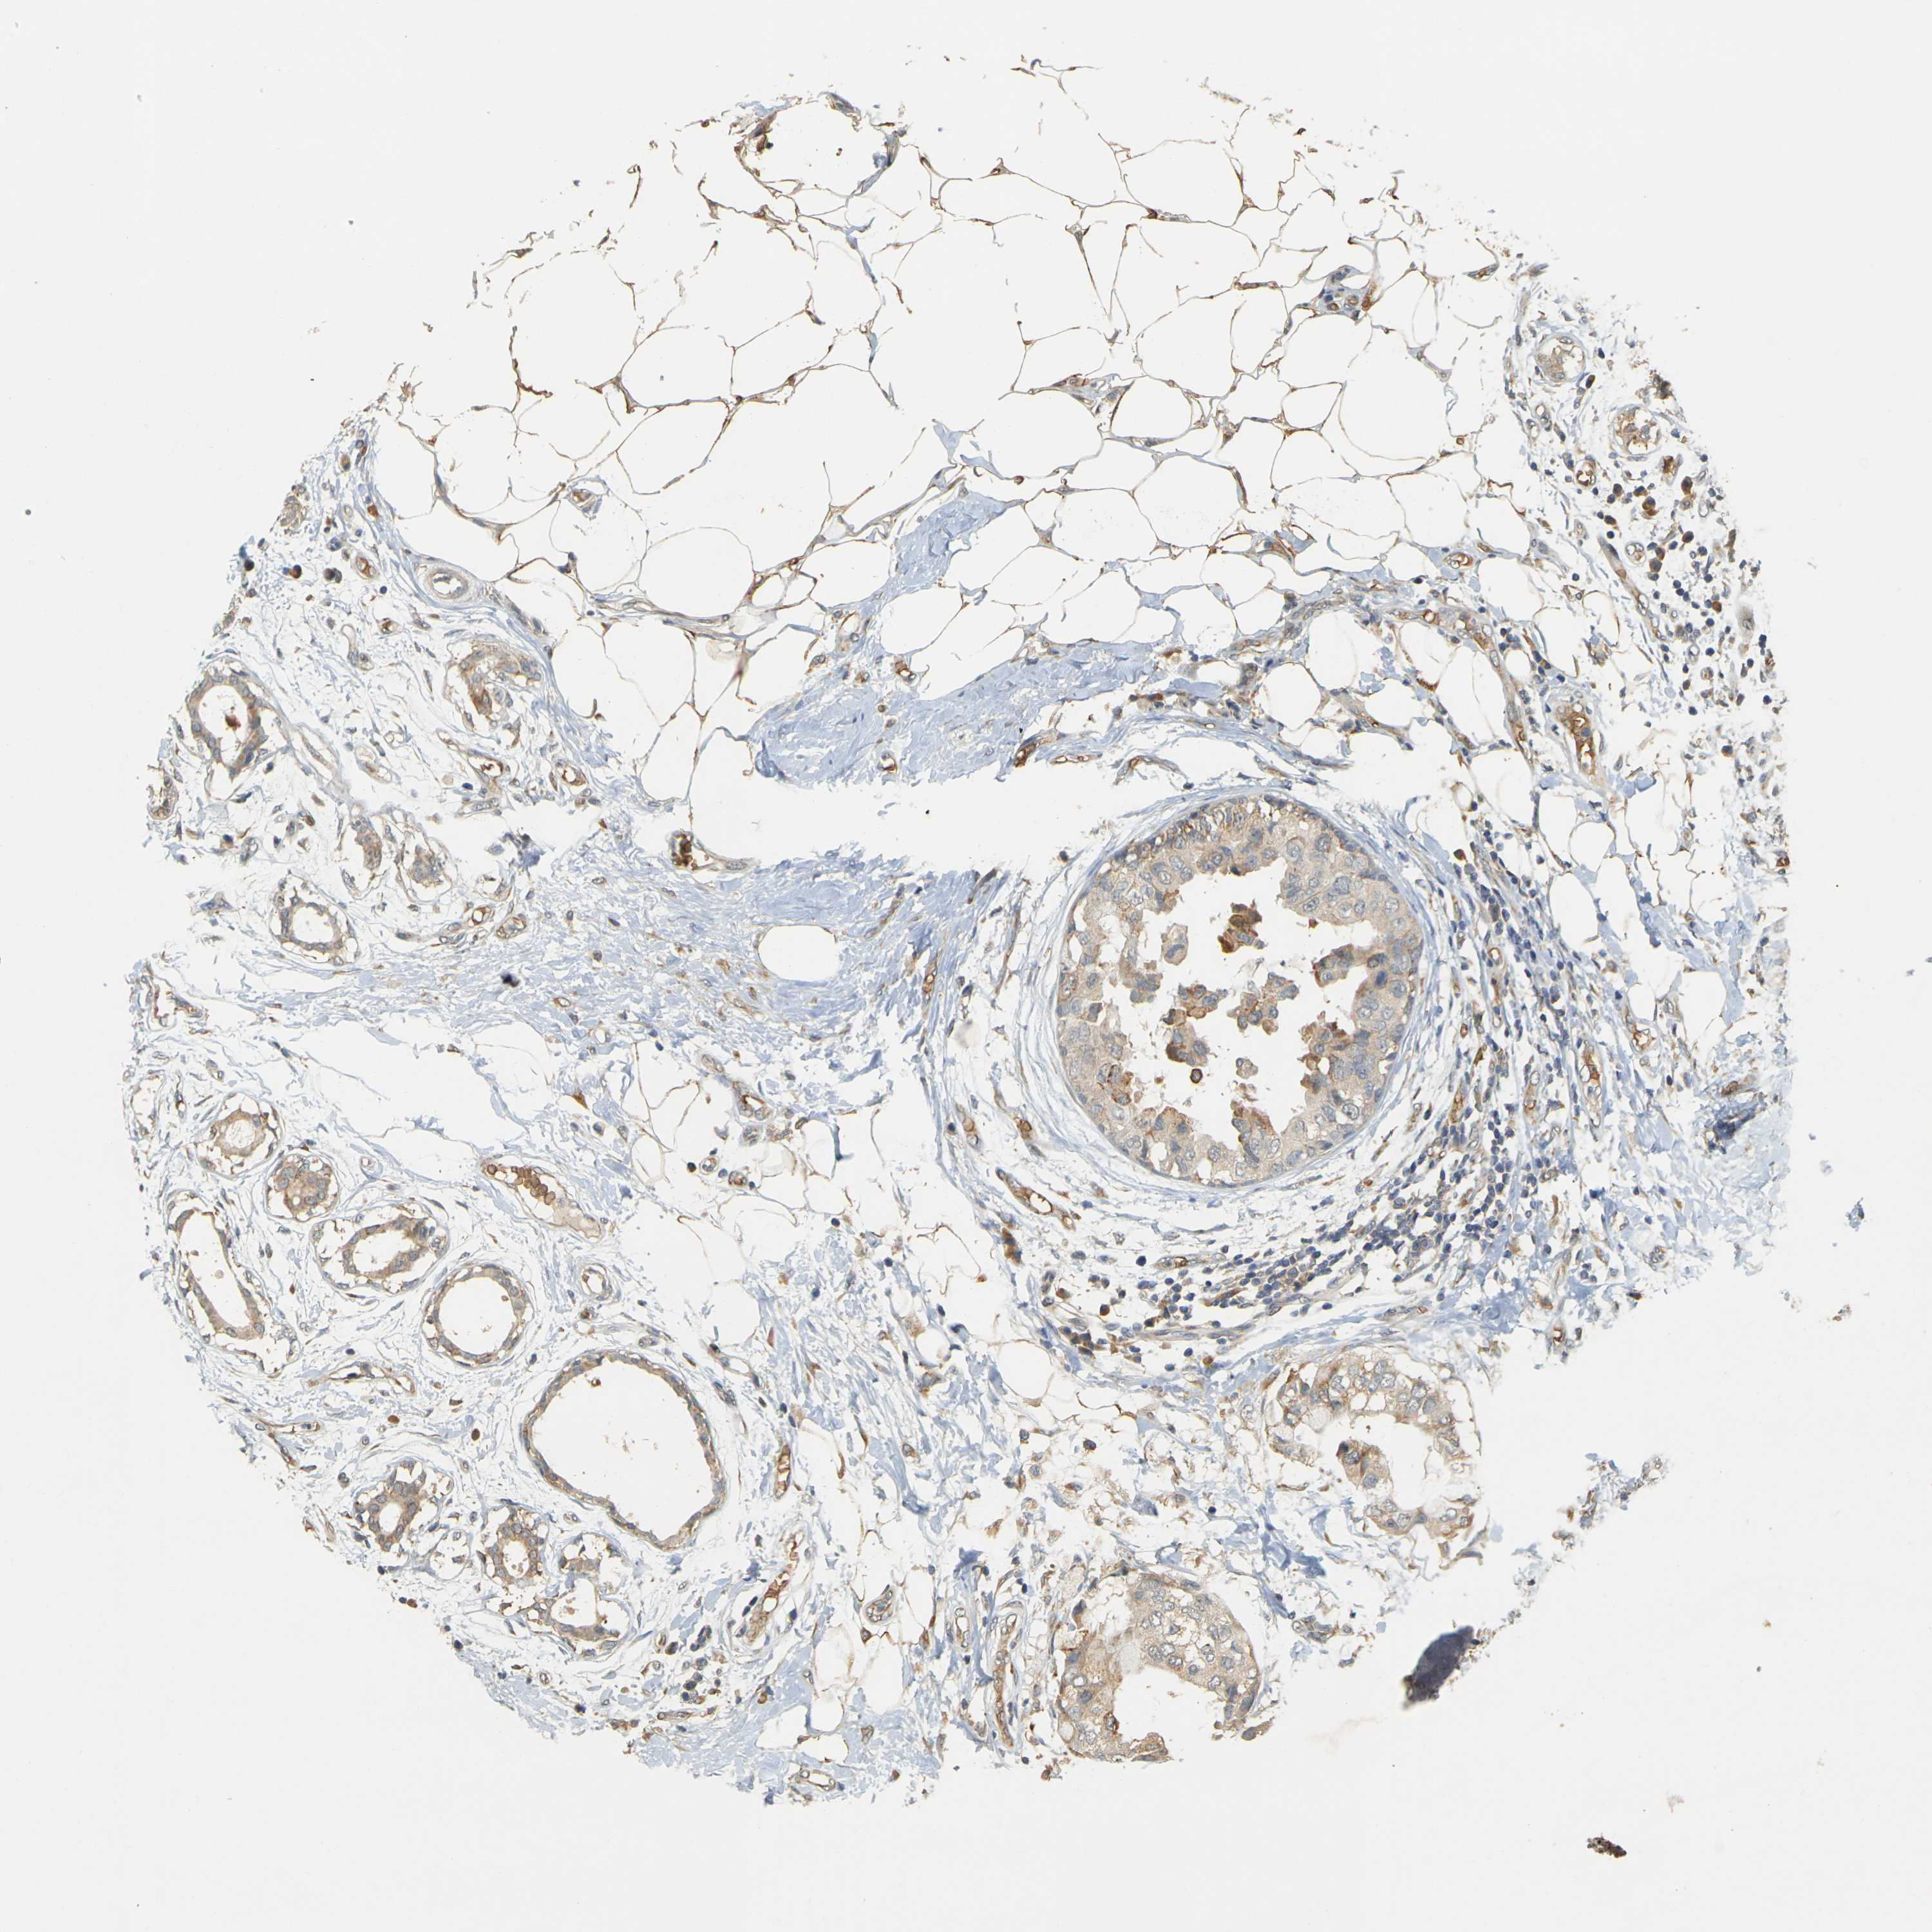

CANCER BREAST CANCER Show tissue menu

BRCA TCGA BRCA VALIDATION PROTEIN EXPRESSION